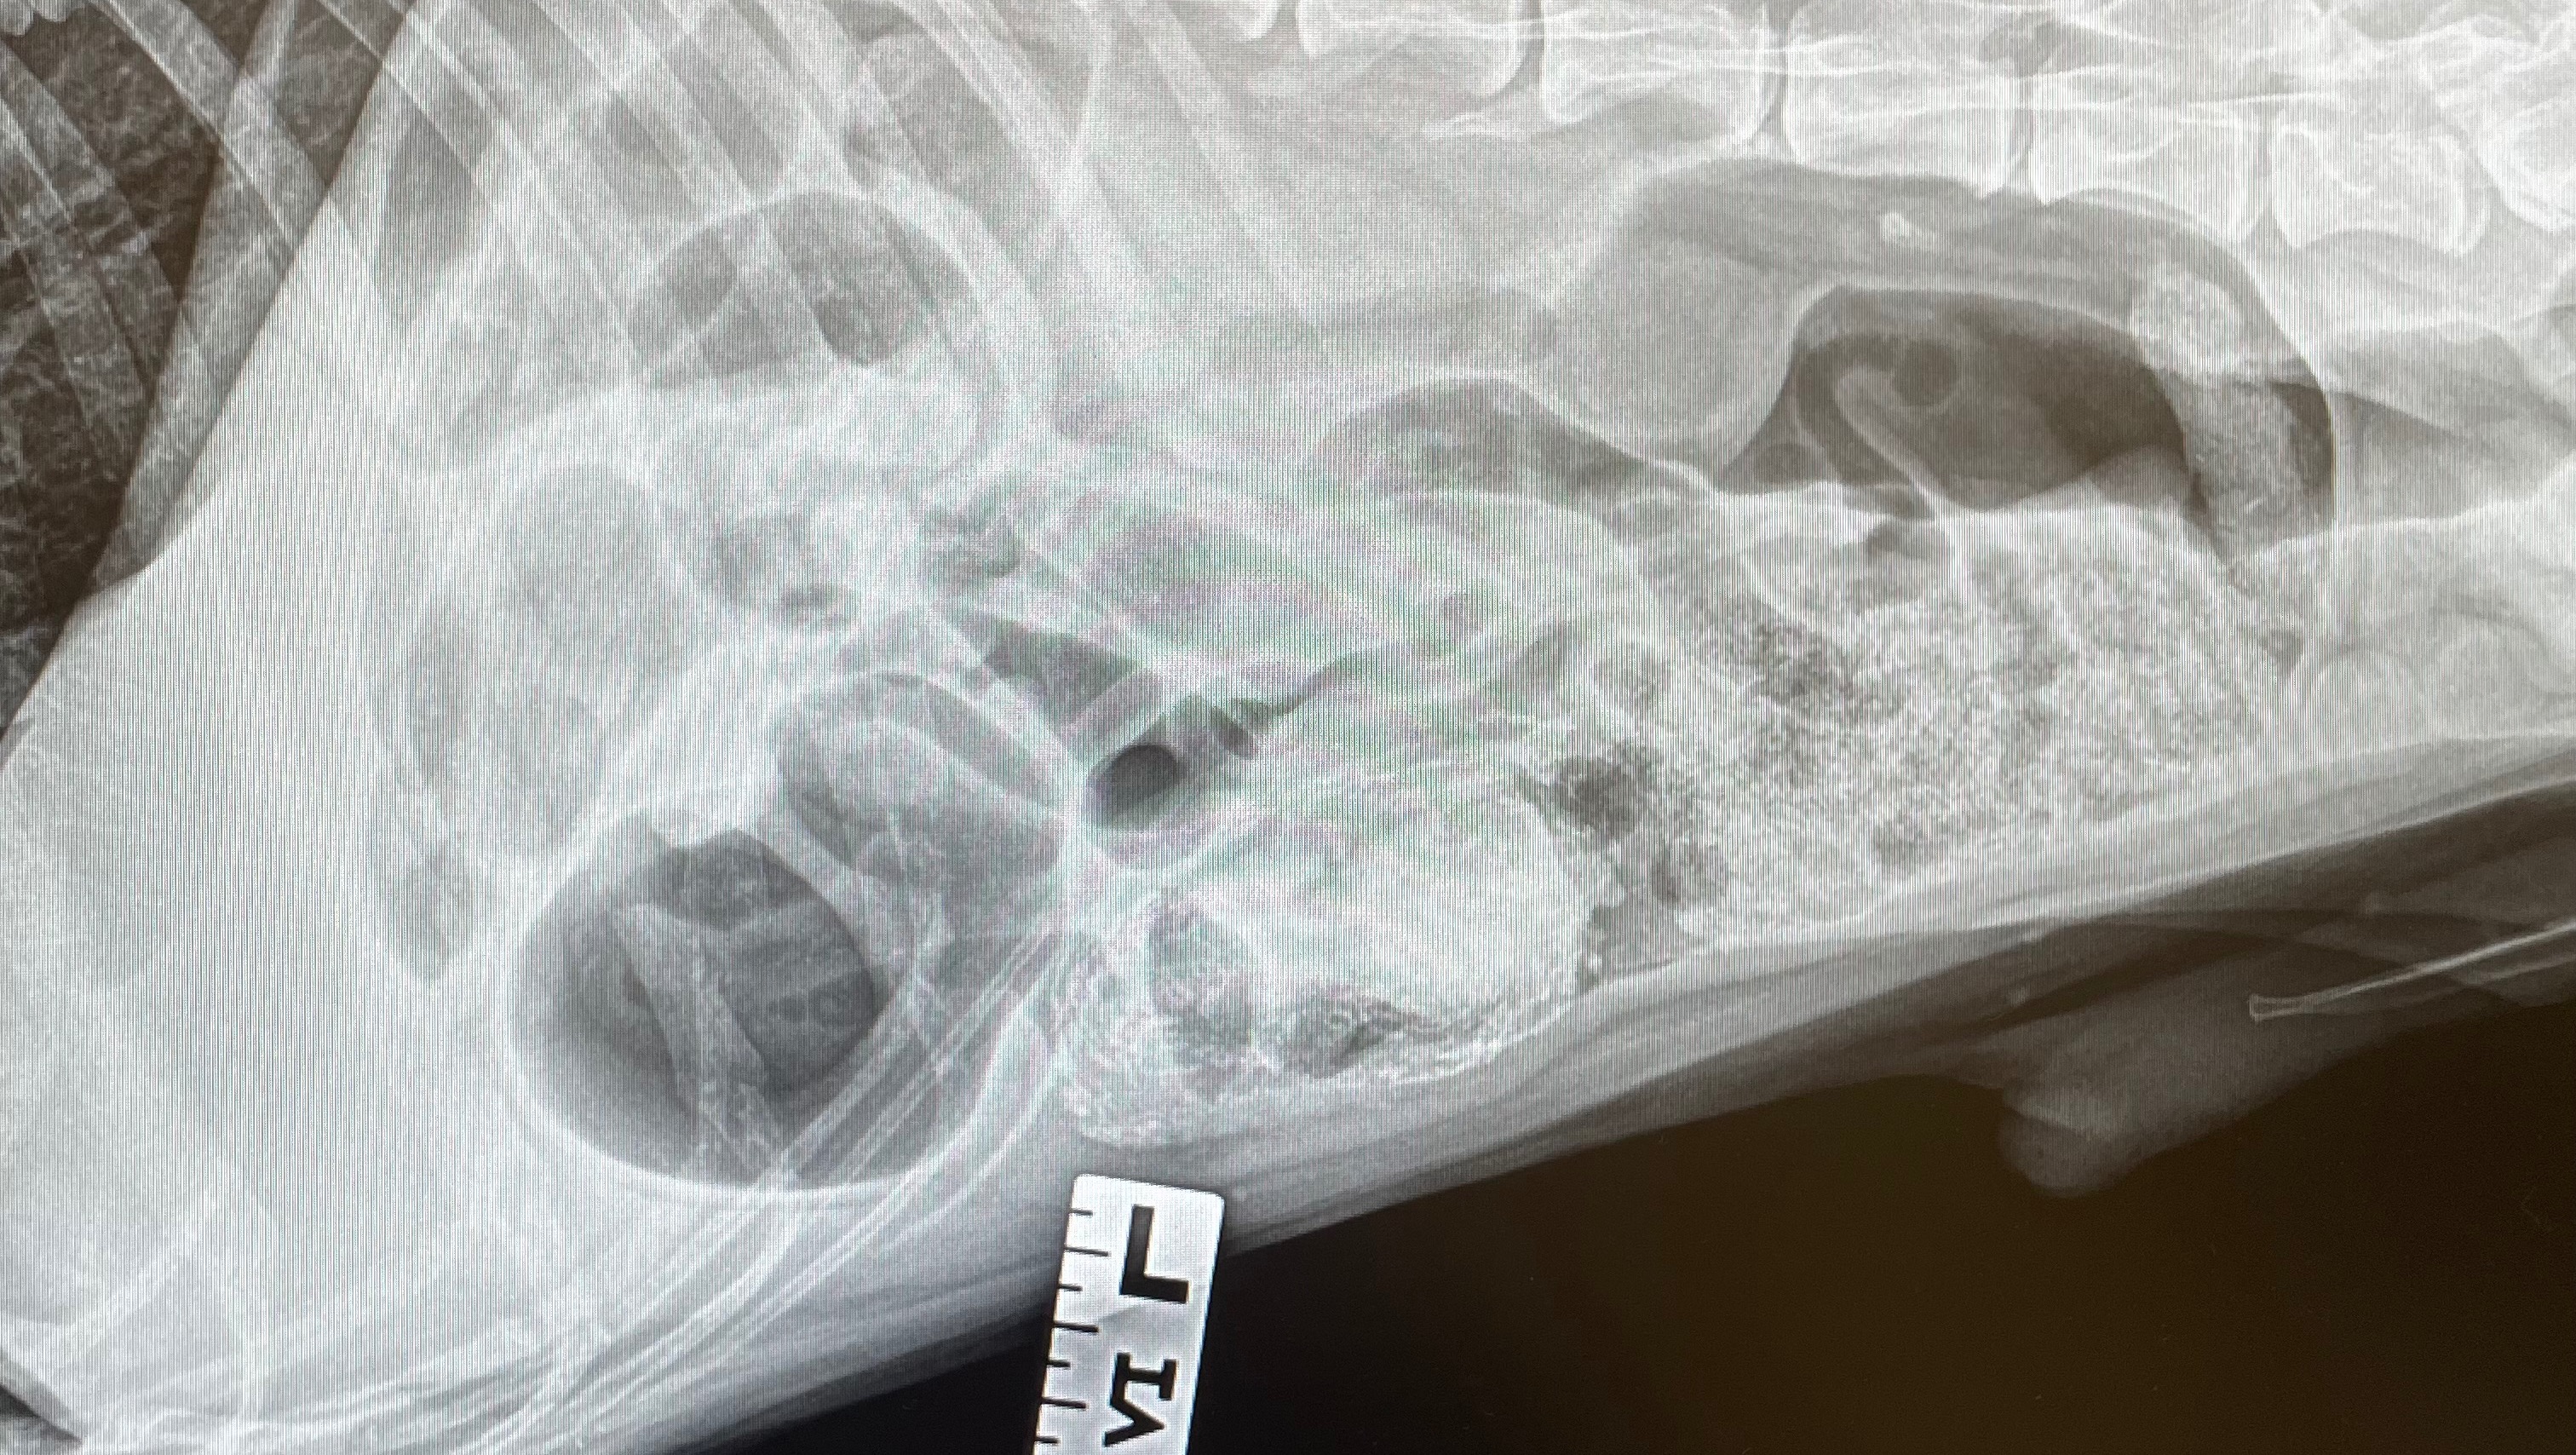

Hi everyone. My dear friends Savannah and her fiance Garrett are going through a really tough time right now with their pup Behr. Within the last two weeks he has developed some really distressing symptoms and stopped eating. After getting several opinions, X-rays and an ultrasound the vets have found that he has, what they expect to be a foreign object, creating a blockage in his intestines. He is very uncomfortable and the only way to save him is to do an emergency exploratory surgery to remove the blockage. Behr is the very best boy (He didn’t even need to be sedated for his imaging because he held so still!) There’s never a good time for something this tragic to happen but over Christmas just makes everything more difficult. Anyone who knows Sav knows that she is a super giving person and her and Garrett will do anything they can to help their boy get through this but they need our help to make it possible! Let’s rally for them and Behr like I know they would for anyone else in this predicament.